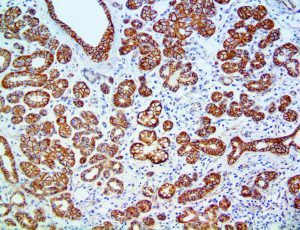

This activation induces inflammatory monocytes to highly express IL-6, starting a localized and then systemic cascade effect that results in hyperproduction of IL-6, which accelerates the inflammatory process. Because IL-6 also increases vascular permeability, excessive levels cause blood vessels to become very leaky. This, along with clotting factors released from vascular endothelial cells, stimulates the coagulation cascade, resulting in microthrombosis (tiny clots), which leads to ischemia and tissue death of the kidney, intestines, heart, liver, brain and extremities.